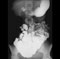

Small intestine Jejunum and ileum Abdominal CT Examine the large intestine; define cecum, appendix, ascending colon, right colic (hepatic) flexure, transverse colon, left colic (splenic) flexure, descending colon, sigmoid colon. Note the characteristics that define and distinguish the large intestine: teniae coli, haustra (sacculations), and omental (epiploic) appendages. What parts of the large intestine are peritoneal; what parts retroperitoneal?

Barium enema of sigmoid colon Abdominal CT Abdominal CT 3. Remove the peritoneum from the right side of the mesentery to expose and identify the superior mesenteric artery and vein and their branches. (Play movie; View images: N 264, 280A, 280B, 281, 300, 301, 302, 306, 307, TG 5-13, 5-14, 5-15, 5-16B, 5-16C, 5-28, 5-34)